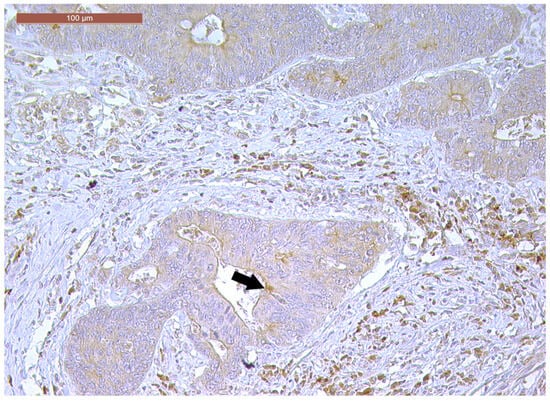

LVI was detected in 31 cases (51.7%), and perineural invasion (PnI) was identified in 20 cases (33.3%) (Figure 1 and Figure 2). EMVI and IMVI were registered in 31 (51.7%) and 21 cases (35%), respectively. Regarding Bd and PDC categories, a significant proportion of tumors were recorded as Bd1, while Bd2 was less common (49 cases; 81.6% vs. 7 cases; 11.7%) (Figure 3); moreover, a large proportion were classed as the PDC1 grade (Figure 4), while the PDC2 grade was less common (55 cases; 91.7% vs. 4 cases; 6.7%). The main clinicopathological characteristics of the study group are summarized in Table 4.

Figure 2. Perineural invasion (arrow) in a ypT3-stage LARC case (H&E staining, 200×).